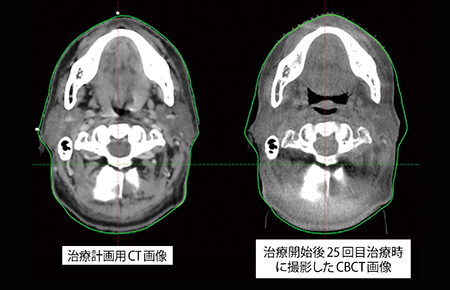

通常,頭頸部癌の治療では,2Gy×35回の分割照射が選択される。正確な放射線治療は,リニアックの照射精度と高い患者セットアップ精度によって実現される。患者セットアップ精度の向上には画像誘導放射線治療(image guided radiation therapy:IGRT)が不可欠であり,画像誘導放射線治療加算が保険収載されていることも後押しとなって,IGRTは多くの施設で実施されている。当院では,「ExacTrac」(ブレインラボ社製)を用いた毎回の2D照合の実施,および1〜5,10,15,20,25,30回目にcone-beam computed tomography(CBCT)の撮影を行い,照射位置の精度確認を行った後,VMAT照射を実施している。CBCT撮影を行うことにより,セットアップ精度の確認だけでなく,患者体重の減少による体型変化および臓器の体積変化を定期的に把握することが可能であり,将来的にCBCTを利用した適応放射線治療(adaptive radiation therapy:ART)の実施が期待される(図3)。

図3 治療計画用CT画像と治療開始後25回目のCBCT画像

治療計画CTの体輪郭(緑ライン)に対して治療開始後25回目のCBCT画像では,体重減少による患者左右方向の体輪郭の変化が確認できる。